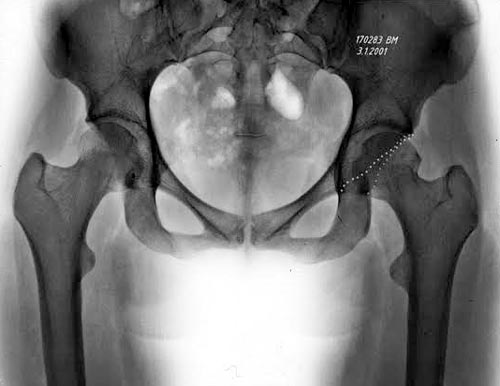

Здесь представлены рентген, боковой, МРТ и клинические снимки

деламинации хряща одного того же пациента.

Имя     : Hip Impingement Xray 1.jpg

Тип     : image/jpeg

Размер  : 38634 байтов

Описание: отсутствует

Url     : http://weborto.net:8080/pipermail/ortho/attachments/20160418/78e1d55d/attachment-0008.jpg